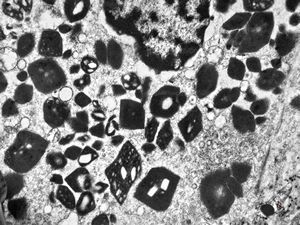

M,58y. | crystalline inclusions in hepatocyte after unknown medication